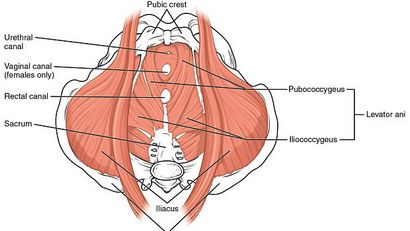

Les exercices de Kegel peuvent aider à renforcer vos muscles du plancher pelvien, qui soutiennent le rectum, de la vessie, de l'utérus et du vagin. Kegels sont particulièrement utiles pour les groupes de femmes ci-dessous:

En ce qui concerne la façon de faire Kegels pour les femmes, vous devez tout d'abord savoir comment identifier les muscles du plancher pelvien chez les femmes, contrat ainsi que les détendre.

1. Trouver les muscles du plancher pelvien

En outre, vous pouvez localiser vos muscles du plancher pelvien en arrêtant votre urine mi-débit. Les muscles qui utilisent pour cette action sont en fait les muscles du plancher pelvien. En outre, obtenir clairement comment il se sent quand contraction et de relaxation.

En bref, les exercices de Kegel sont être effectués en appuyant sur les muscles du plancher pelvien et la tenue pendant une courte période de temps. La clé pour faire ces exercices correctement est d'isoler vos muscles du plancher pelvien, ainsi que les utiliser seul. Il est très facile de serrer les muscles de l'abdomen et les fesses en même temps. Par conséquent, faites attention au corps et être sûr que vous travaillez vos muscles.